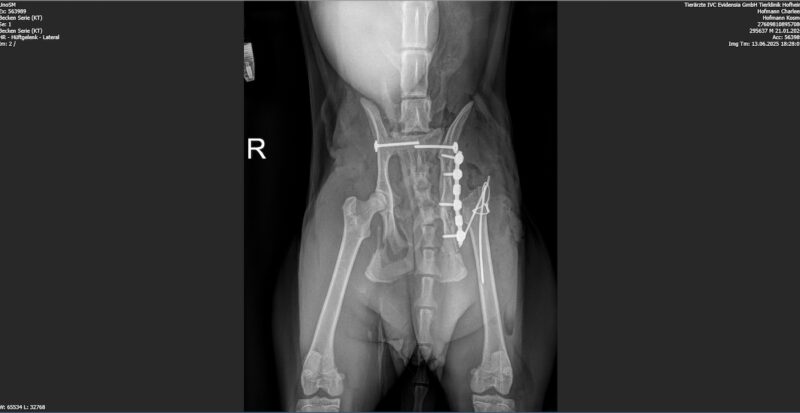

Die Bildgebung ergab multiple Beckenfrakturen, beidseitige Iliosakralgelenksluxationen, eine Beteiligung des linken Acetabulums, eine Läsion des linken Femurkopfes sowie eine mögliche Schwanzablösung im Bereich der ersten beiden Schwanzwirbel. Am Folgetag erfolgte die operative Versorgung mit bilateraler Stabilisierung der Iliosakralgelenke, Versorgung der Iliumfraktur inklusive Trochanter-Osteotomie und einer Femurkopf-Hals-Resektion links. Fünf Tage später wurde Kosmo zur physiotherapeutischen Erstvorstellung überwiesen.